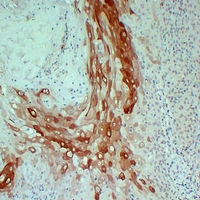

(Immunohistochemical analysis of Cytokeratin 10 staining in human cutaneous squamous cell carcinomas formalin fixed paraffin embedded tissue section. The section was pre-treated using heat mediated antigen retrieval with sodium citrate buffer (pH 6.0). The section was then incubated with the antibody at room temperature and detected using an HRP conjugated compact polymer system. DAB was used as the chromogen. The section was then counterstained with haematoxylin and mounted with DPX.)